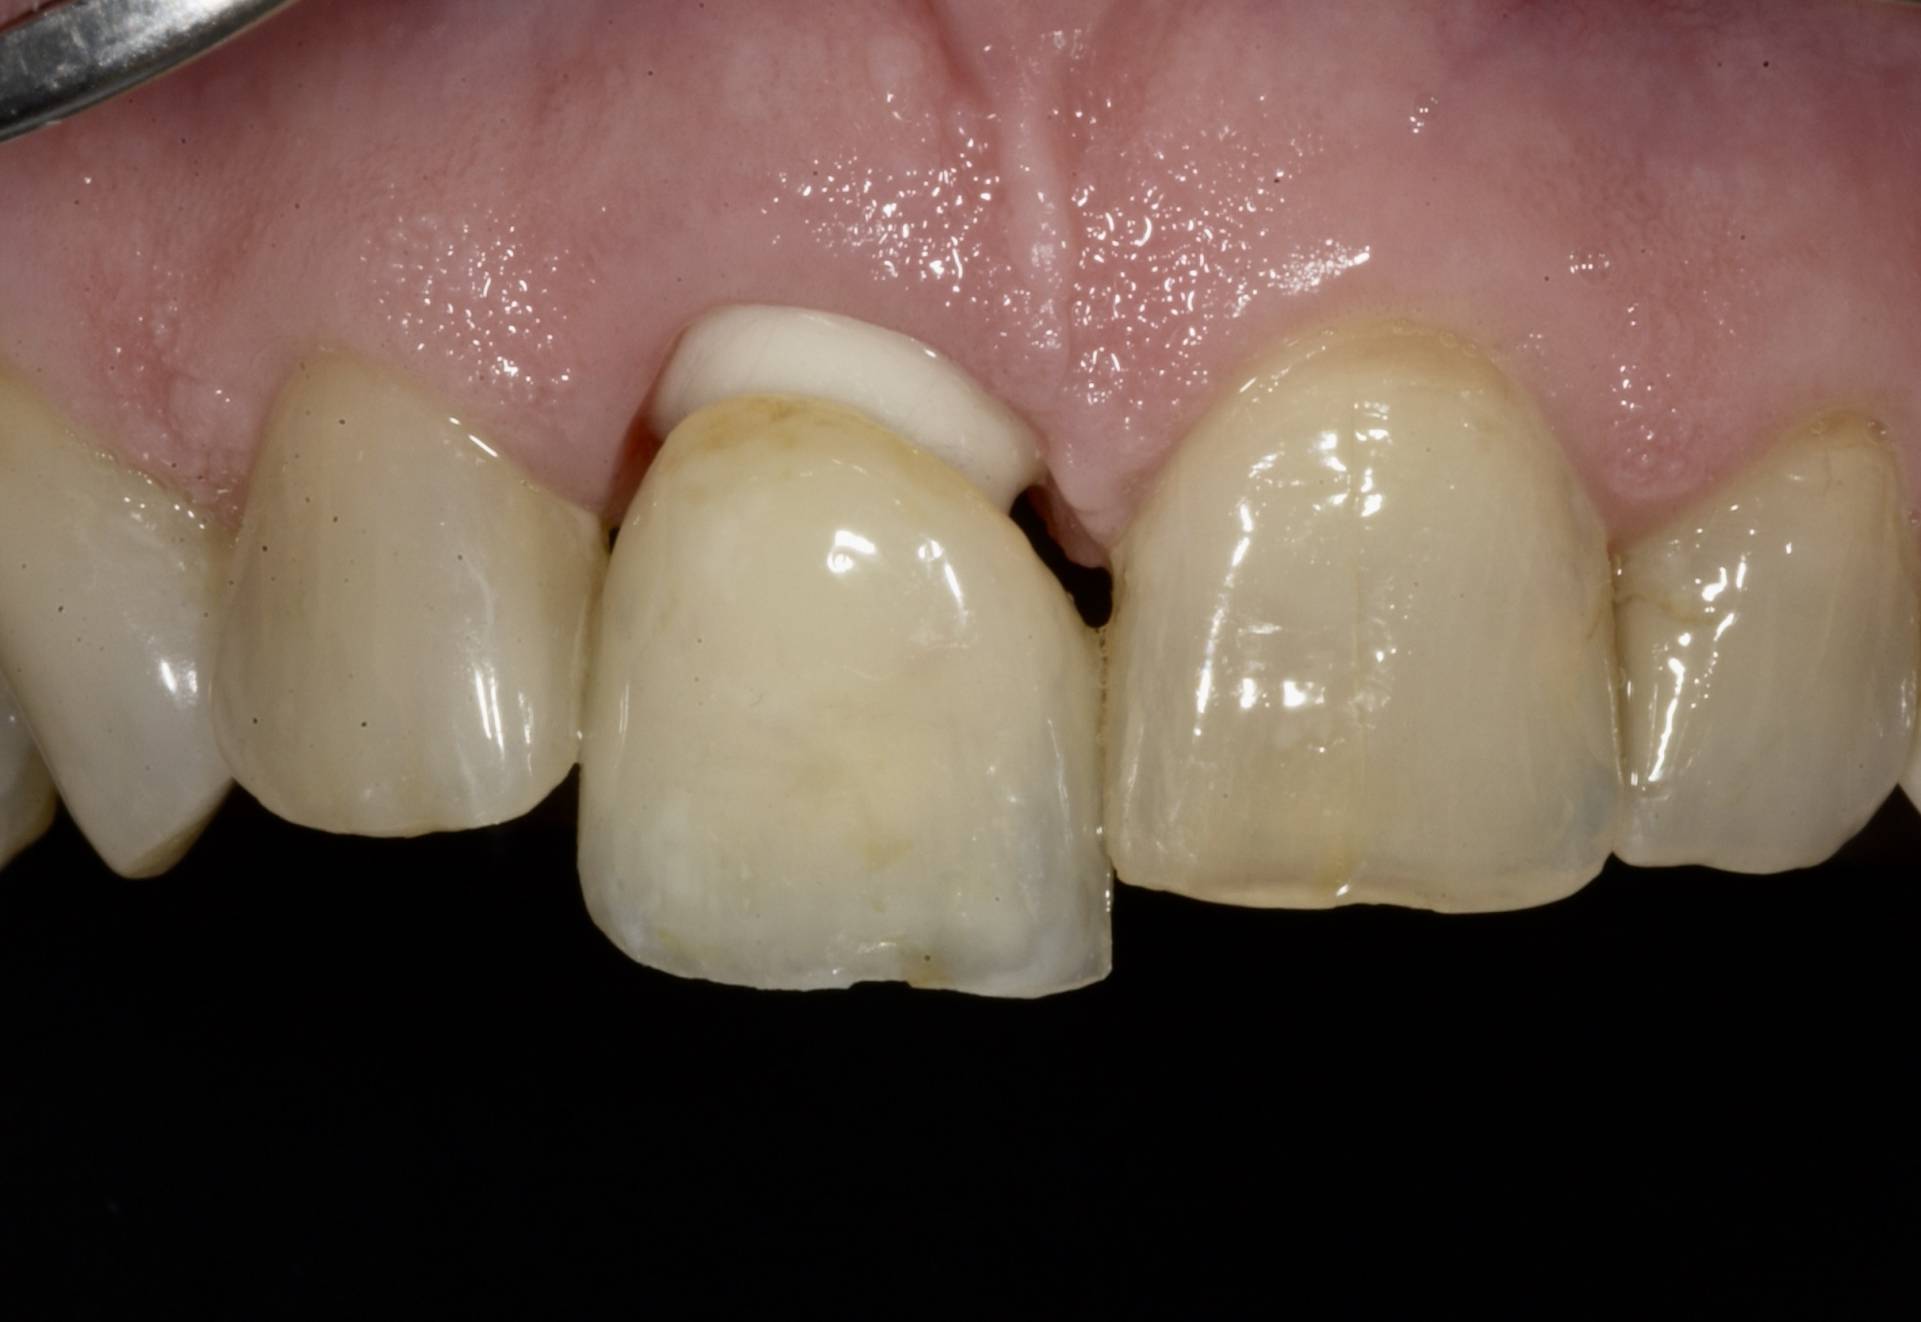

Mithilfe moderner Diagnostik, mikrochirurgischer Techniken und gewebeschonender Verfahren schaffen wir optimale Voraussetzungen für eine sichere Einheilung. Bei Bedarf werden knochenaufbauende Maßnahmen und biologische Regenerationskonzepte integriert, um auch in anspruchsvollen Situationen stabile Ergebnisse zu erzielen.

Das Ziel ist eine funktionell und ästhetisch perfekte Versorgung, die sich harmonisch in das bestehende Gebiss einfügt – für langfristige Stabilität, Sicherheit und ein natürliches Gefühl beim Kauen und Sprechen.